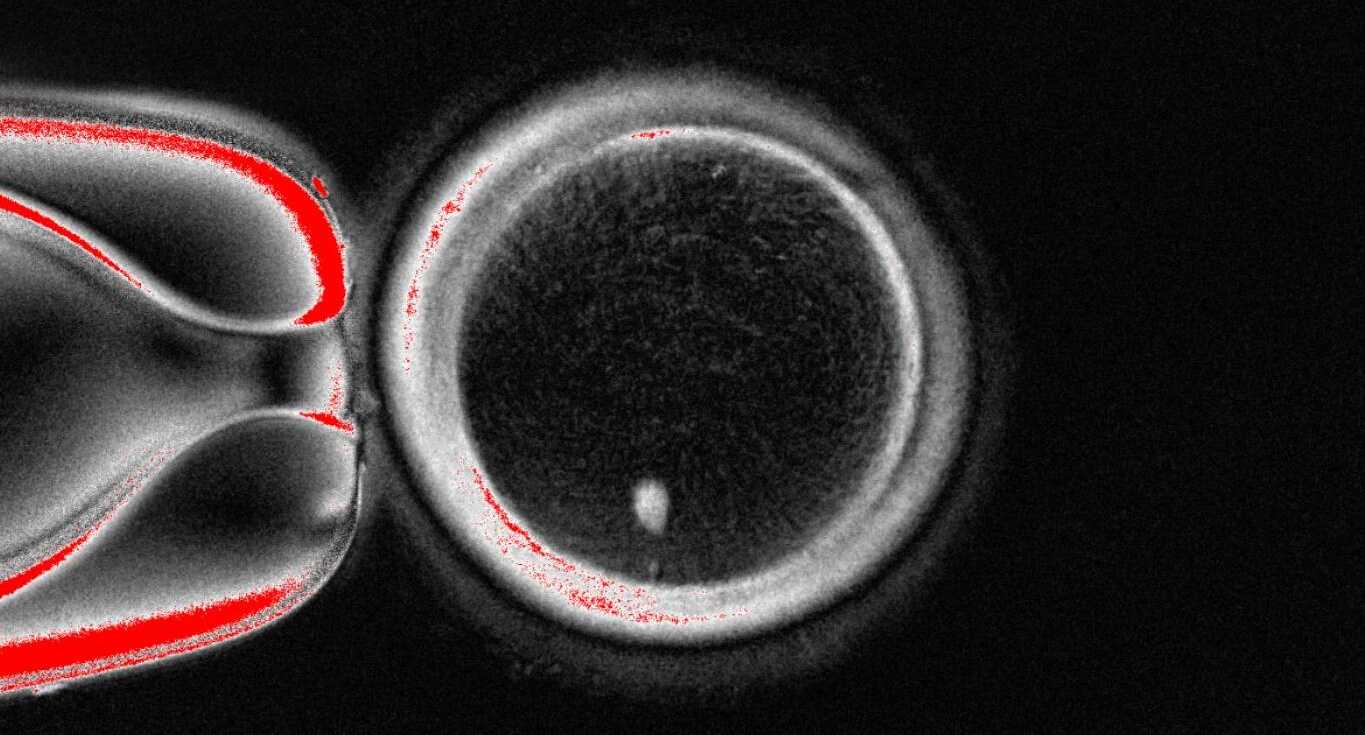

В новом исследовании Миталипов с коллегами перешел к экспериментам с человеческими клетками. У зрелых яйцеклеток, взятых у здоровых женщин, остановленных в фазе MII и содержащих полярное тельце первого деления, удалили комплексы веретен с хромосомами и перенесли в них остановленные на фазе G0/G1 ядра фибробластов человеческой кожи. После этого в них происходило преждевременное наступление метафазы без предварительной фазы S с формированием веретена деления de novo примерно через два часа после переноса. Эти клетки оплодотворили сперматозоидами методом ИКСИ, после чего 23,4 процента из них выделили полярное тельце и 17,4 процента сформировали пронуклеусы (против 82,9 и 79,8 процента у контрольных оплодотворенных яйцеклеток). Лишь 25 процентов от этого числа начали дробиться (против 100 процентов контрольных), однако процесс останавливался на стадии двух клеток, то есть окончательного выхода из фазы MII не последовало.

Чтобы решить эту проблему, исследователи разработали метод искусственной активации яйцеклеток, который состоит в их электропорации в D-сорбитовом буфере с ионами кальция (симулирующей повышение внутриклеточного уровня кальция после естественного оплодотворения) с последующим ингибированием митоз-стимулирующего фактора (MPF) росковитином. После этой процедуры 8,8 процента яйцеклеток с перенесенными ядрами развивались в бластоцисты.